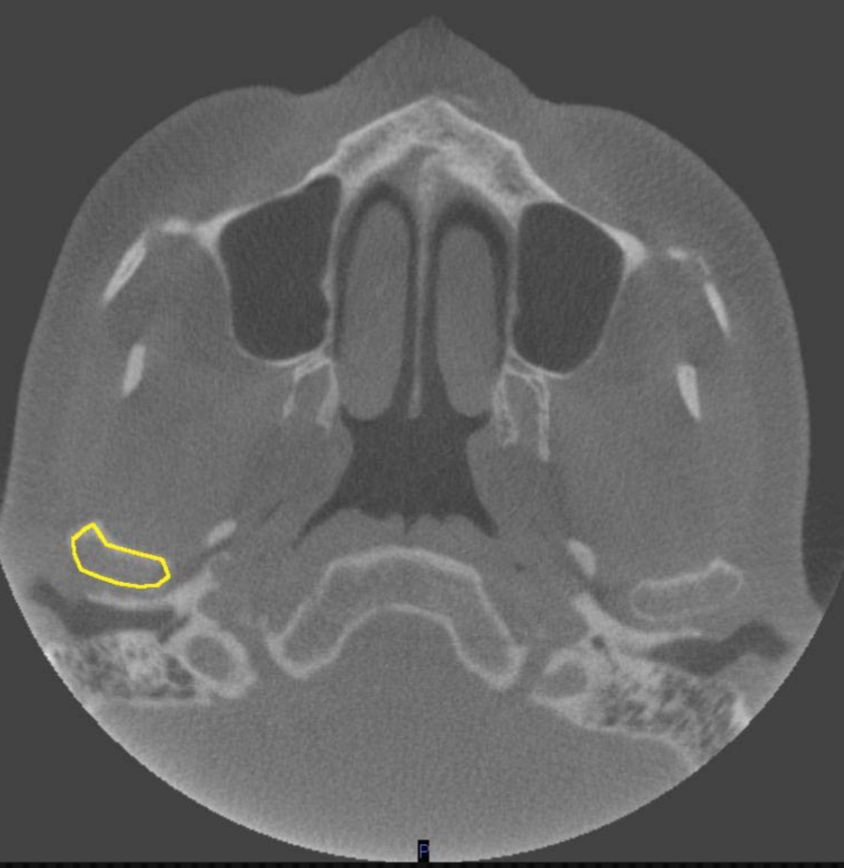

zygomatic arch

what is indicated by the YELLOW